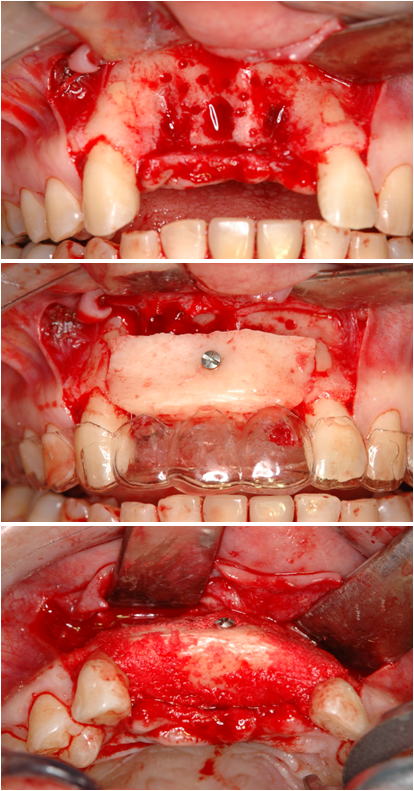

4.極度の骨・軟組織欠損がある2歯欠損症例

(他院でトラブルとなった症例 2の再インプラント治療、自家骨移植と有茎口蓋弁移植)

まず予後不良インプラント撤去し、極度の骨欠損があったが、オトガイ部から10mmの厚みの皮質海綿ブロック骨移植にて審美的インプラント治療を行いました。歯肉の厚みを増やすために有茎口蓋弁移植も併用しました。